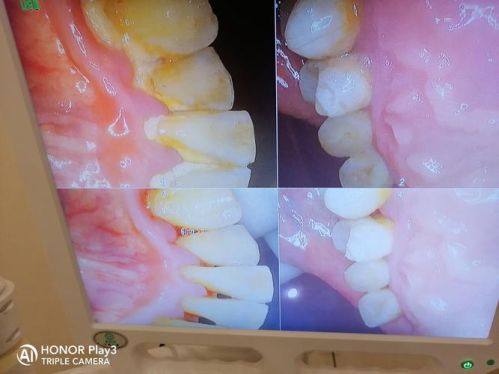

2. 牙齿美学修复:陶医生在牙齿美学修复方面有着丰富的经验,她能够通过烤瓷牙、全冠牙、固定义齿、活动义齿、嵌体修复等多种修复方式,改善牙齿的外观和功能。在修复过程中,她会结合患者的面部比例和口腔情况,设计出更适合患者的修复方案,让患者的牙齿看起来更加自然美观,同时也能修复牙齿的咀嚼功能。

5. 牙列缺损/缺失的修复及牙种植术:当患者出现牙列缺损或缺失的情况时,陶医生会根据患者的具体情况,选择合适的修复方式,如种植牙、烤瓷牙、活动义齿等。其中,种植牙是一种精良的牙齿修复技术,陶医生在种植牙方面有着丰富的经验。她能够熟练掌握种植牙的操作技巧,确保种植牙的成功几率和稳定性。种植牙不仅能够修复牙齿的咀嚼功能,还能保持面部的自然美观,让患者重拾自信。

2. 患者张女士牙齿有缺损,影响了美观和咀嚼功能。她来到正夫口腔寻求帮助,陶胤彤医生为她推荐了种植牙修复方案。在种植牙手术前,陶医生详细地向张女士讲解了手术过程和注意事项,让她消除了紧张情绪。手术过程非常顺利,术后张女士修复得也良好。张女士评价说:“陶医生的技术真的特别棒,手术一点都不疼,而且种的牙齿和我的真牙几乎没有区别,现在我吃东西也方便多了。我会把她推荐给身边有需要的人。”